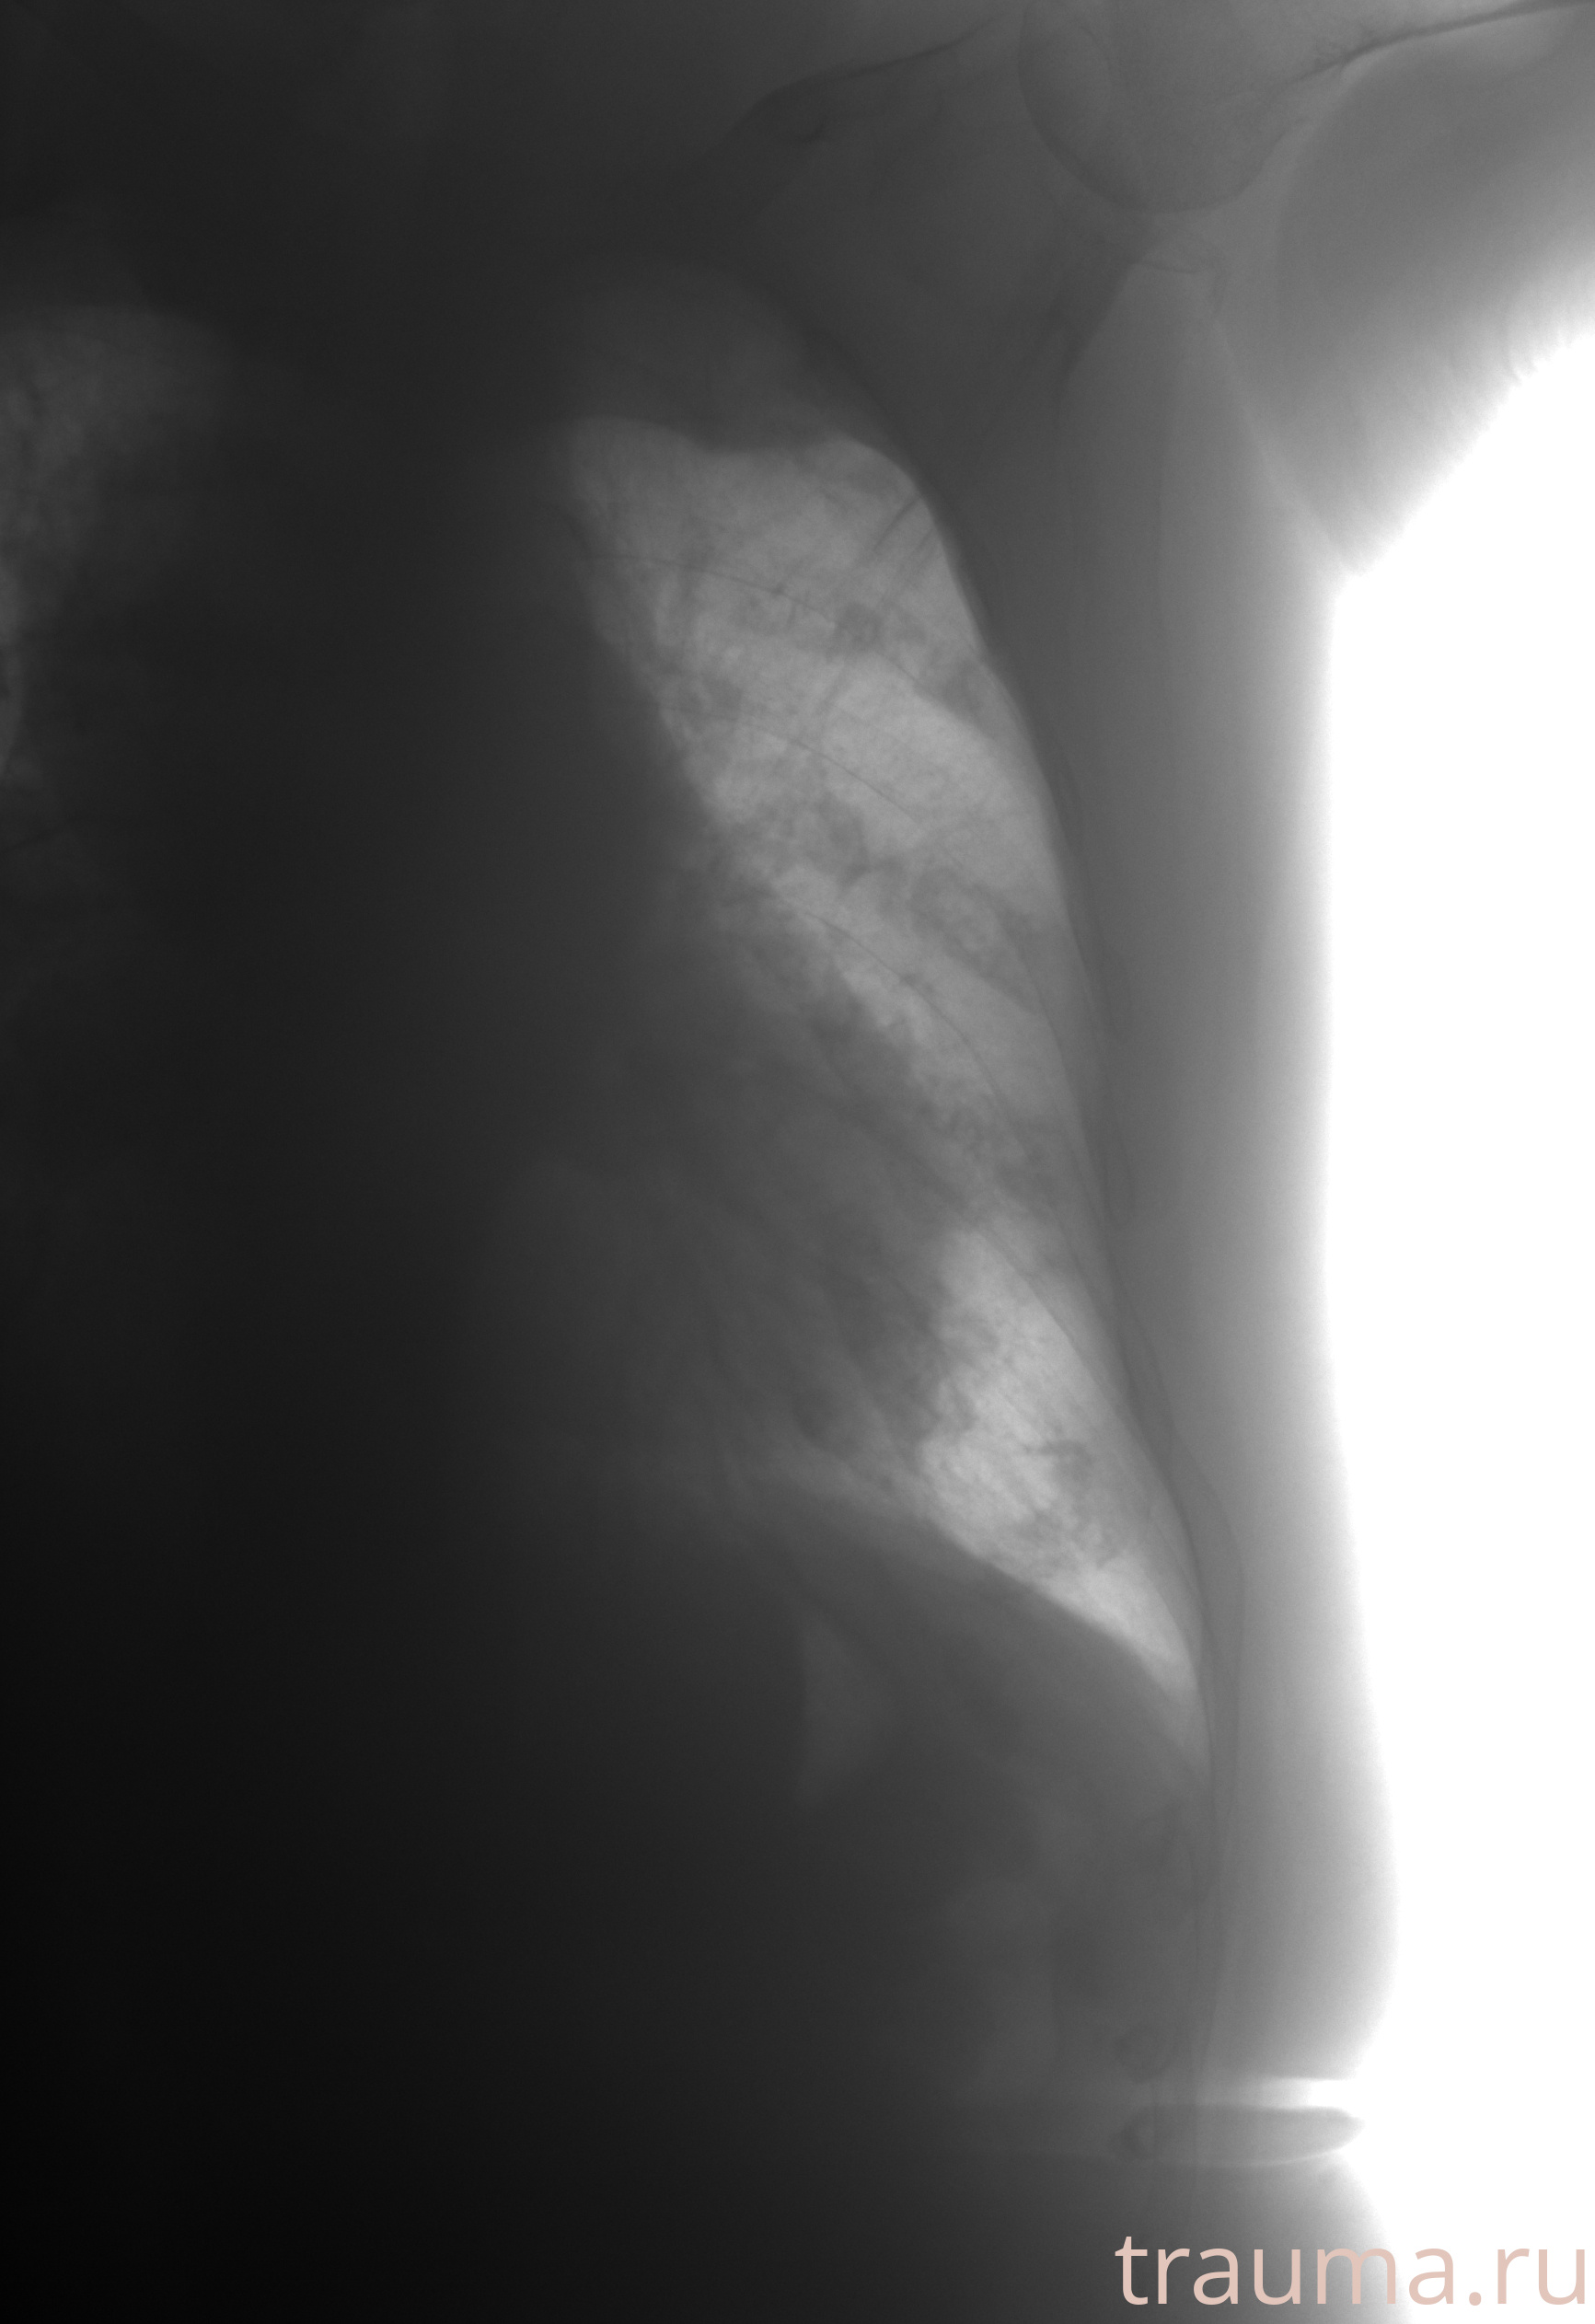

Рентген на дому: по вашему адресу приезжает врач-рентгенолог, травматолог-ортопед с мобильным рентгеновским аппаратом, проводит диагностику травмы или заболевания, делает необходимые рентгенограммы, дает рекомендации по дальнейшему лечению. Получить качественные снимки в домашних условиях возможно благодаря уникальной методике, разработанной МосРентген Центром для института  Склифосовского

при переломе шейки бедра и пневмонии от компании МосРентген Центр - партнера Института имени Склифосовского